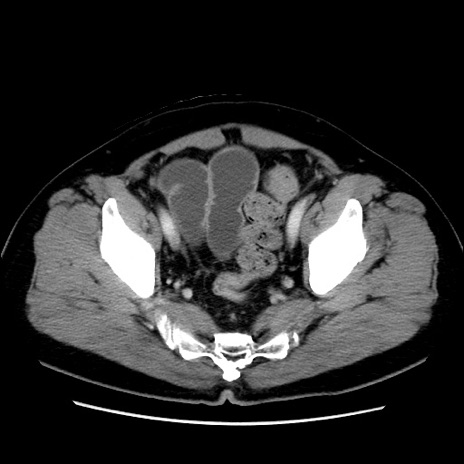

症例16(横断像)

【症例】 70歳代男性

【主訴】 腹痛、嘔吐

【現病歴】 約1ヶ月前より間欠的に腹痛と嘔吐あり、当院消化器内科を受診したところCTで多発する肝臓のLDAを指摘され、精査中であった。以降は消化器症状は安定していたが、2日前より嘔気と腹痛があり、同日より排便・排ガスが消失した。改善認めず、 本日、救急外来を受診した。

【既往歴】 大腸ポリープ切除後。

【身体所見】意識清明・会話良好、BT 36.3℃、BP 127/80mmHg、 P 80bpm、腹部:膨満あり、平坦・軟、上腹部正中および下腹部正中に圧痛あり、反跳痛なし、筋性防御なし。

【データ】WBC 7200、CRP 0.77